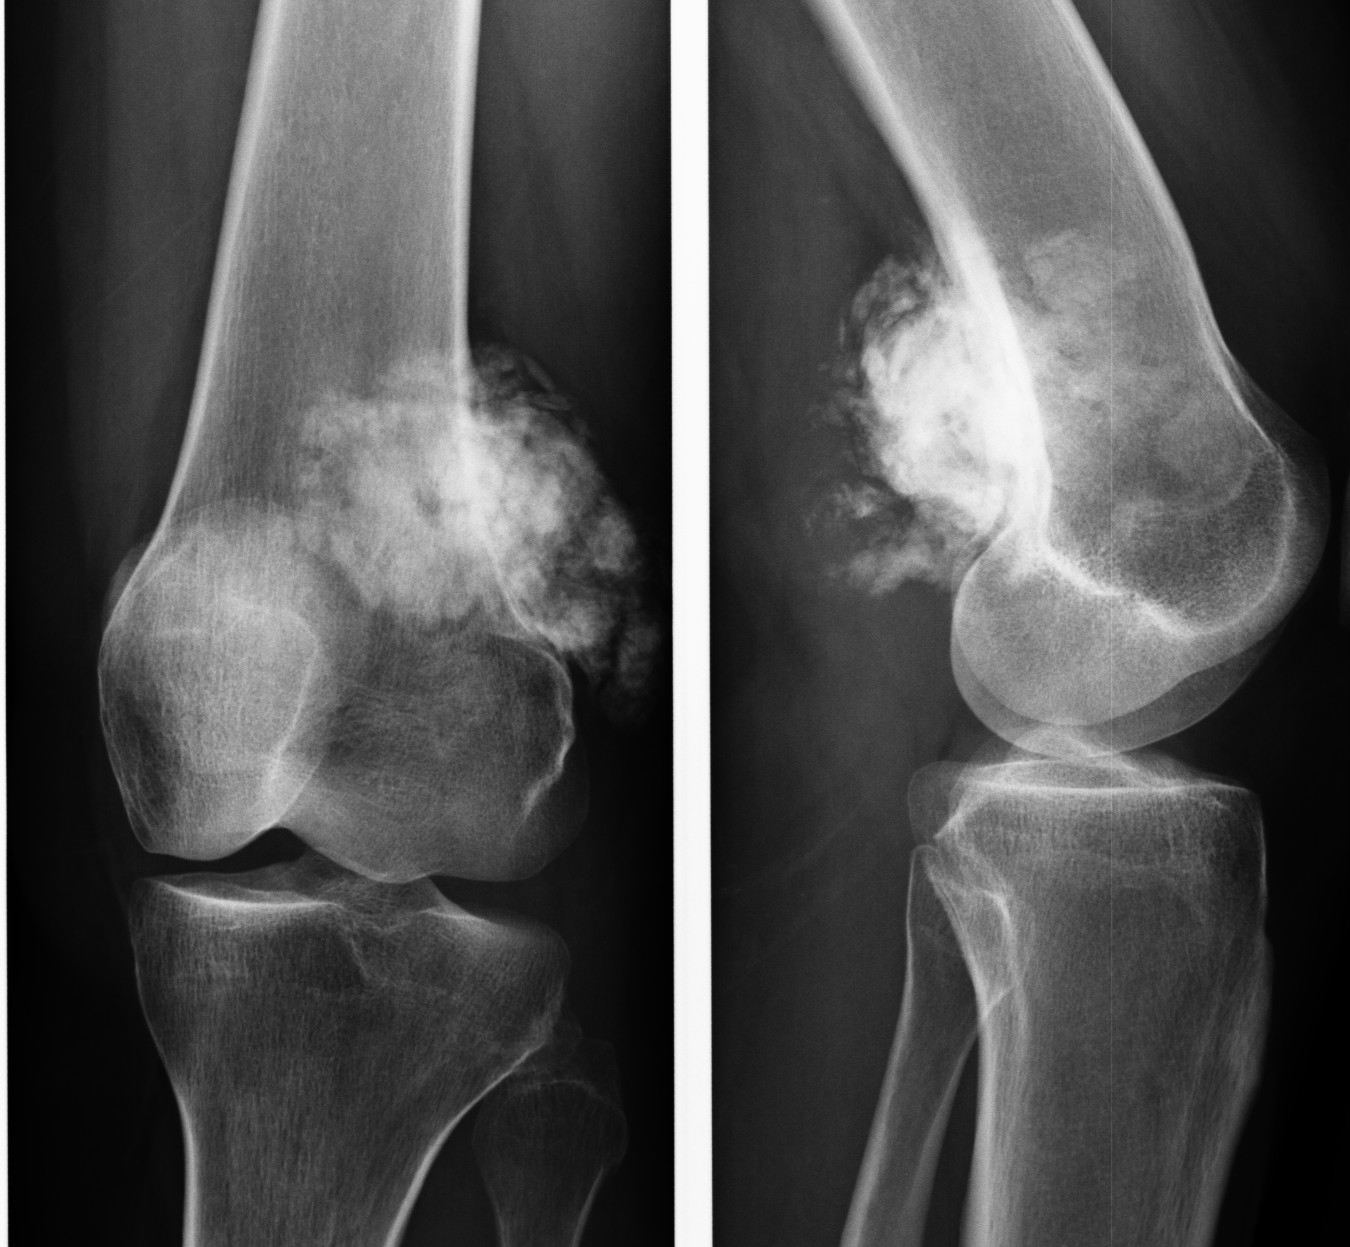

Диагностика остеогенных сарком основывается на рентгенологических и гистопатологических данных. Полный набор методов обследования может включать следующие процедуры:

- Рентгенографическое исследование.

Рентгенография позволяет определить:

- местоположение опухоли;

- наличие склеротических и литических очагов, а также васкуляризацию;

- патологические изменения в мягких тканях, связанные с костями;

- образования на надкостнице в виде “козырьков” и “треугольников Кодмена”;

- игольчатые периоститы, представляющие собой разрастание игольчатых структур перпендикулярно к костям;

- макрометастатические процессы.

Бедренная локализация опухоли

- На ранних этапах заболевания отсутствуют проявления.

- Анальгетики не снимают болевой синдром.

- Ночью боли в ногах усиливаются.

- Увеличиваются размеры пораженной зоны.

- Появляется отечность и припухлость в области поражения.

- На коже возникает венозная сетка.

- Может развиваться хромота.

- Фиксируются переломы в области поражения.